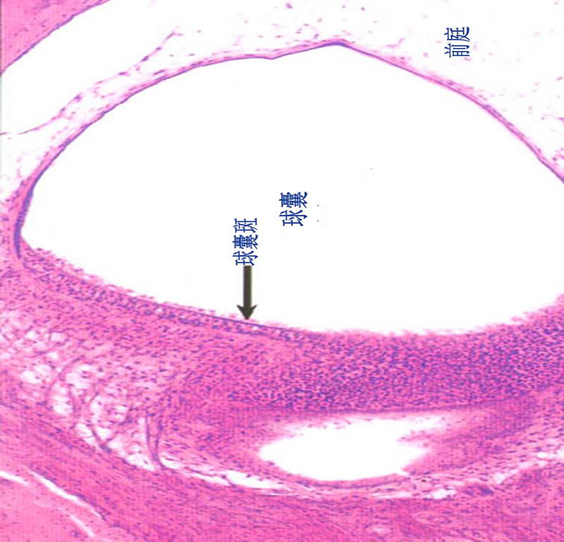

角膜从前至后分为角膜上皮、前界层、角膜基质、后界层和角膜内皮。

1)角膜上皮:未角化的复层扁平上皮。

2)前界层:薄层,含胶原原纤维和基质。

3)角膜基质:占90%,相互垂直的板层,大量平行排列的胶原原纤维和少量成纤维细胞,含较多水分。

4)后界层:与前界层相似,更薄。

5)角膜内皮:单层扁平上皮。

1.角膜上皮;2.前界层;3.角膜基质;↓后界层;↑角膜内皮